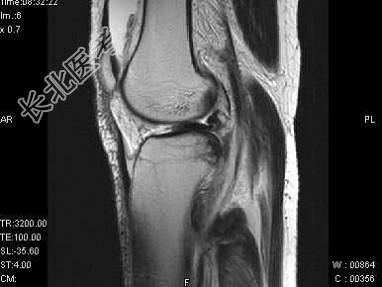

- 单项选择题女,17岁, 右膝关节有外伤史,现膝关节疼痛, 活动受限,结合图像, 最可能的诊断是 ( )

A、半月板撕裂

B、膝关节退变

C、未见异常

D、前交叉韧带断裂

E、后交叉韧带断裂